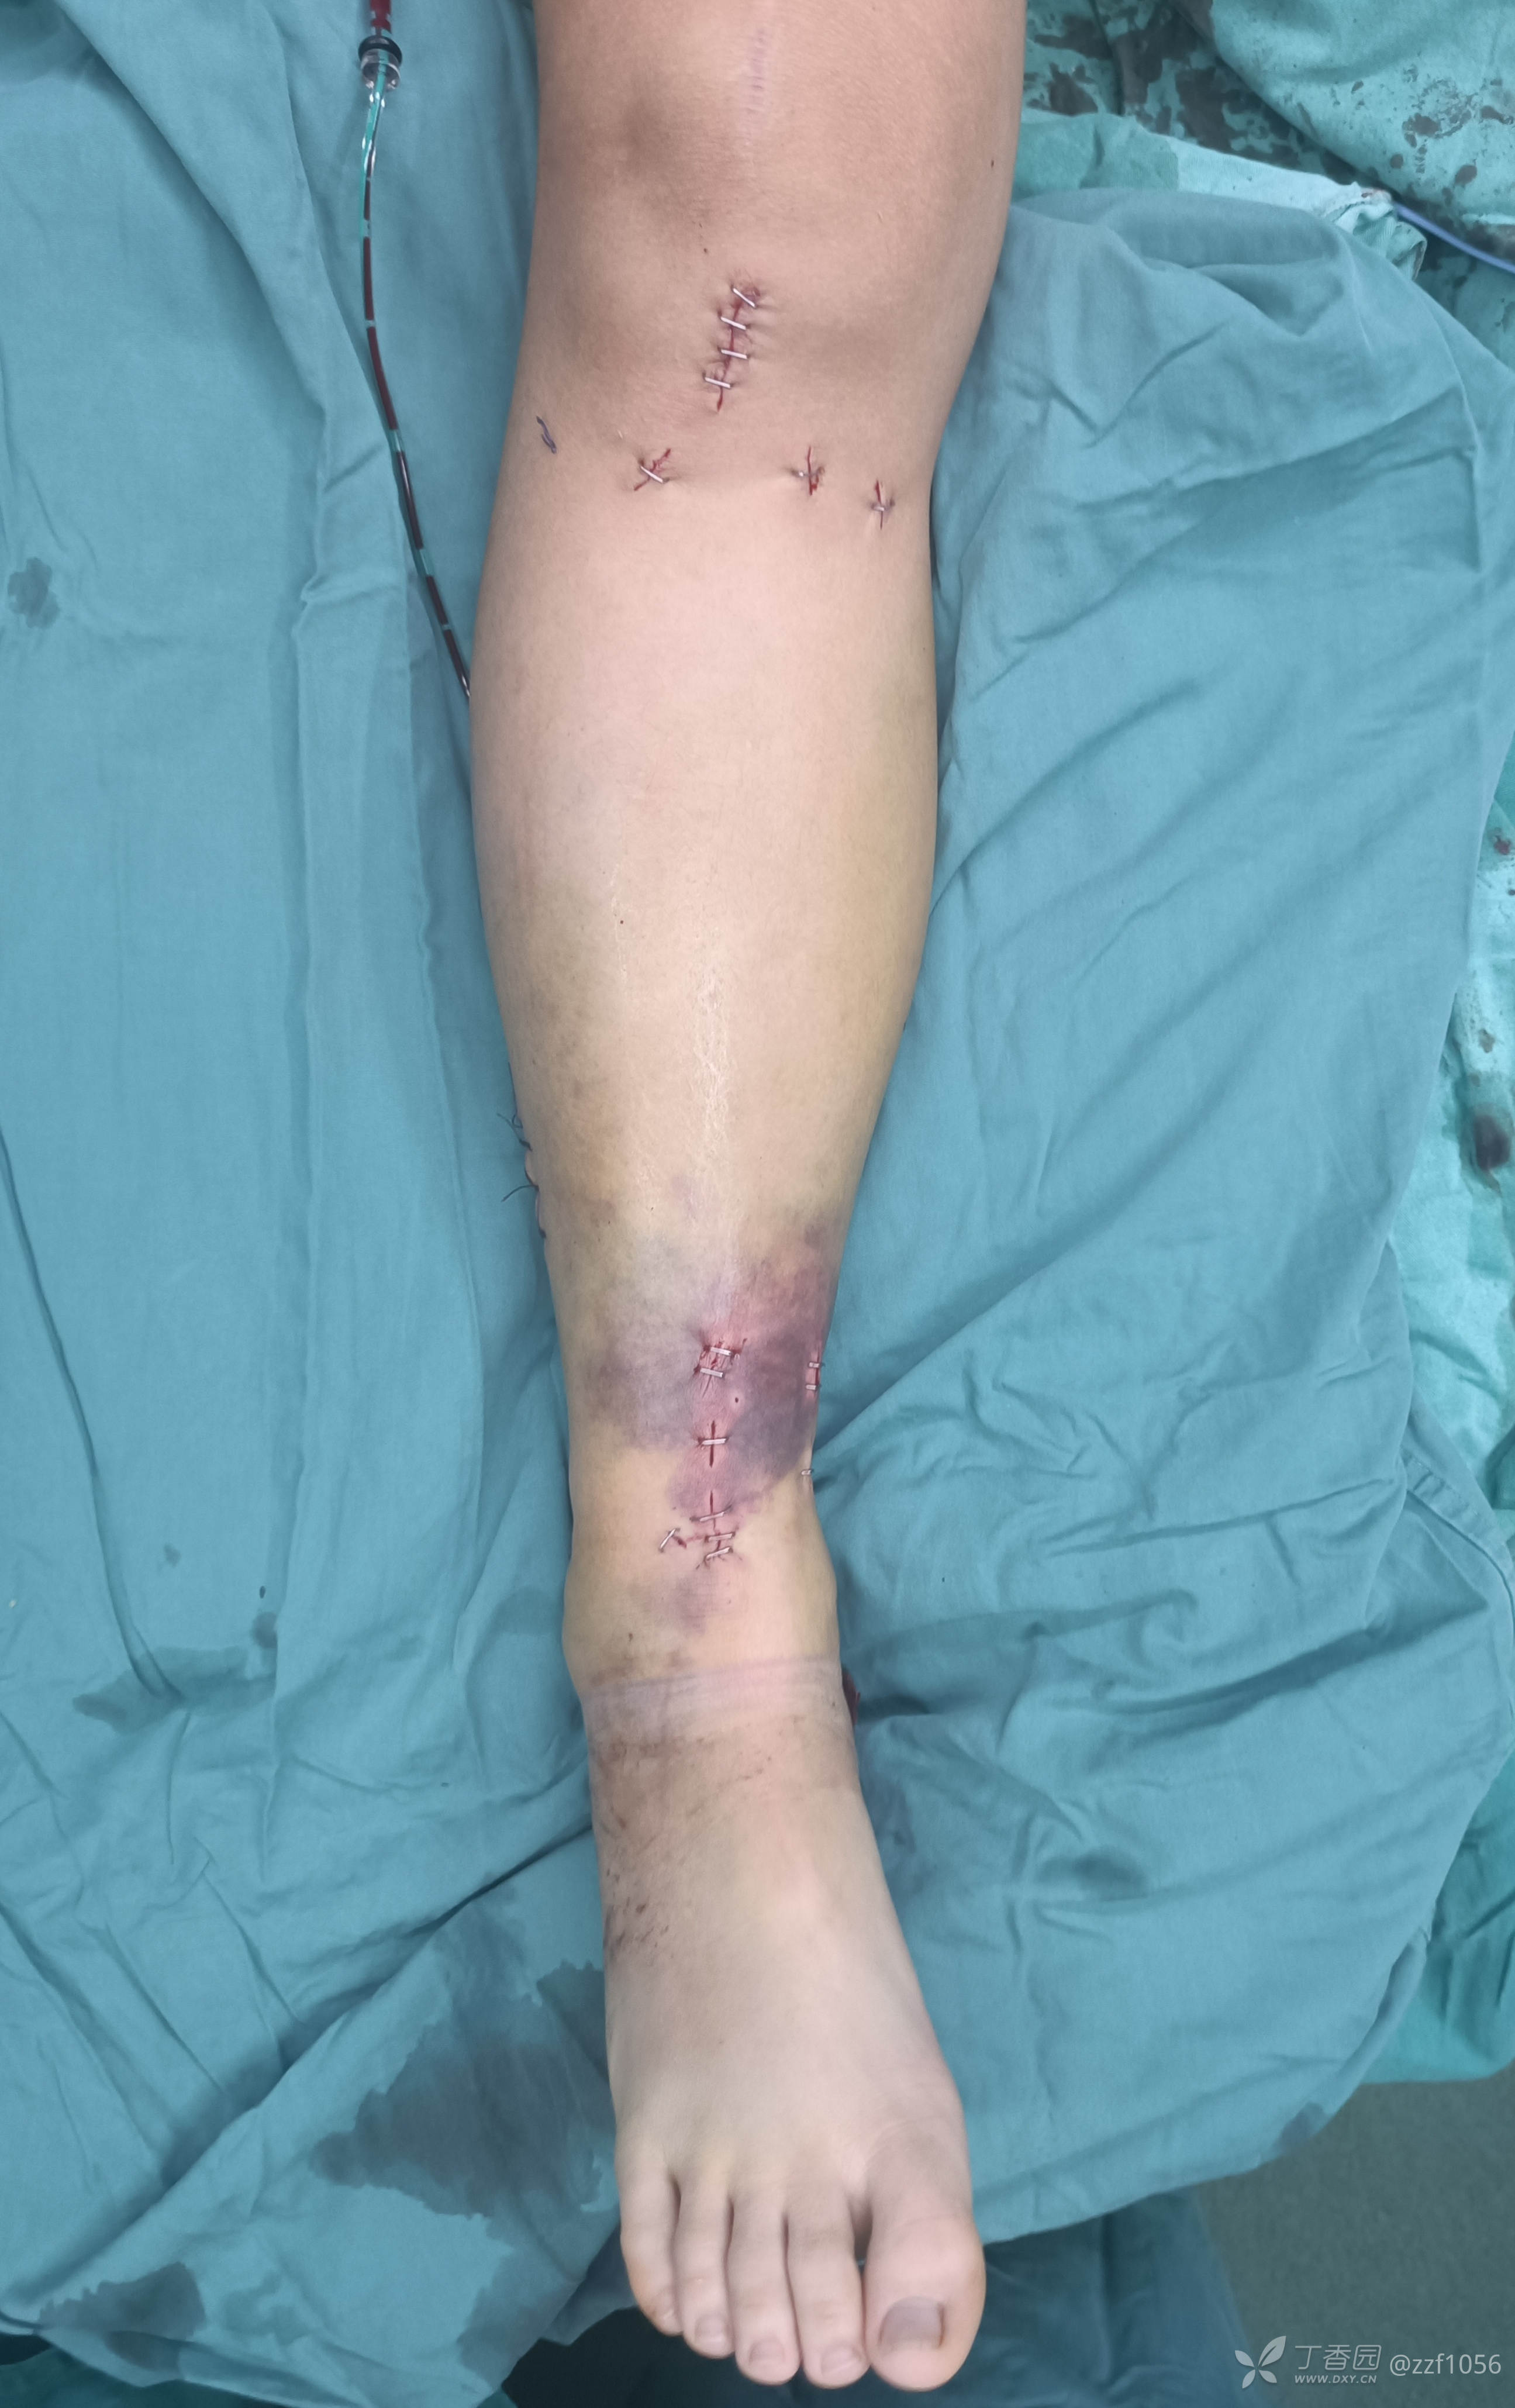

皮肤条件不算太好

术中

克氏针临时固定后踝,阻挡钉技术辅助髓内钉复位纠正成角畸形,您一般用多大的克氏针呢?

术后效果显著